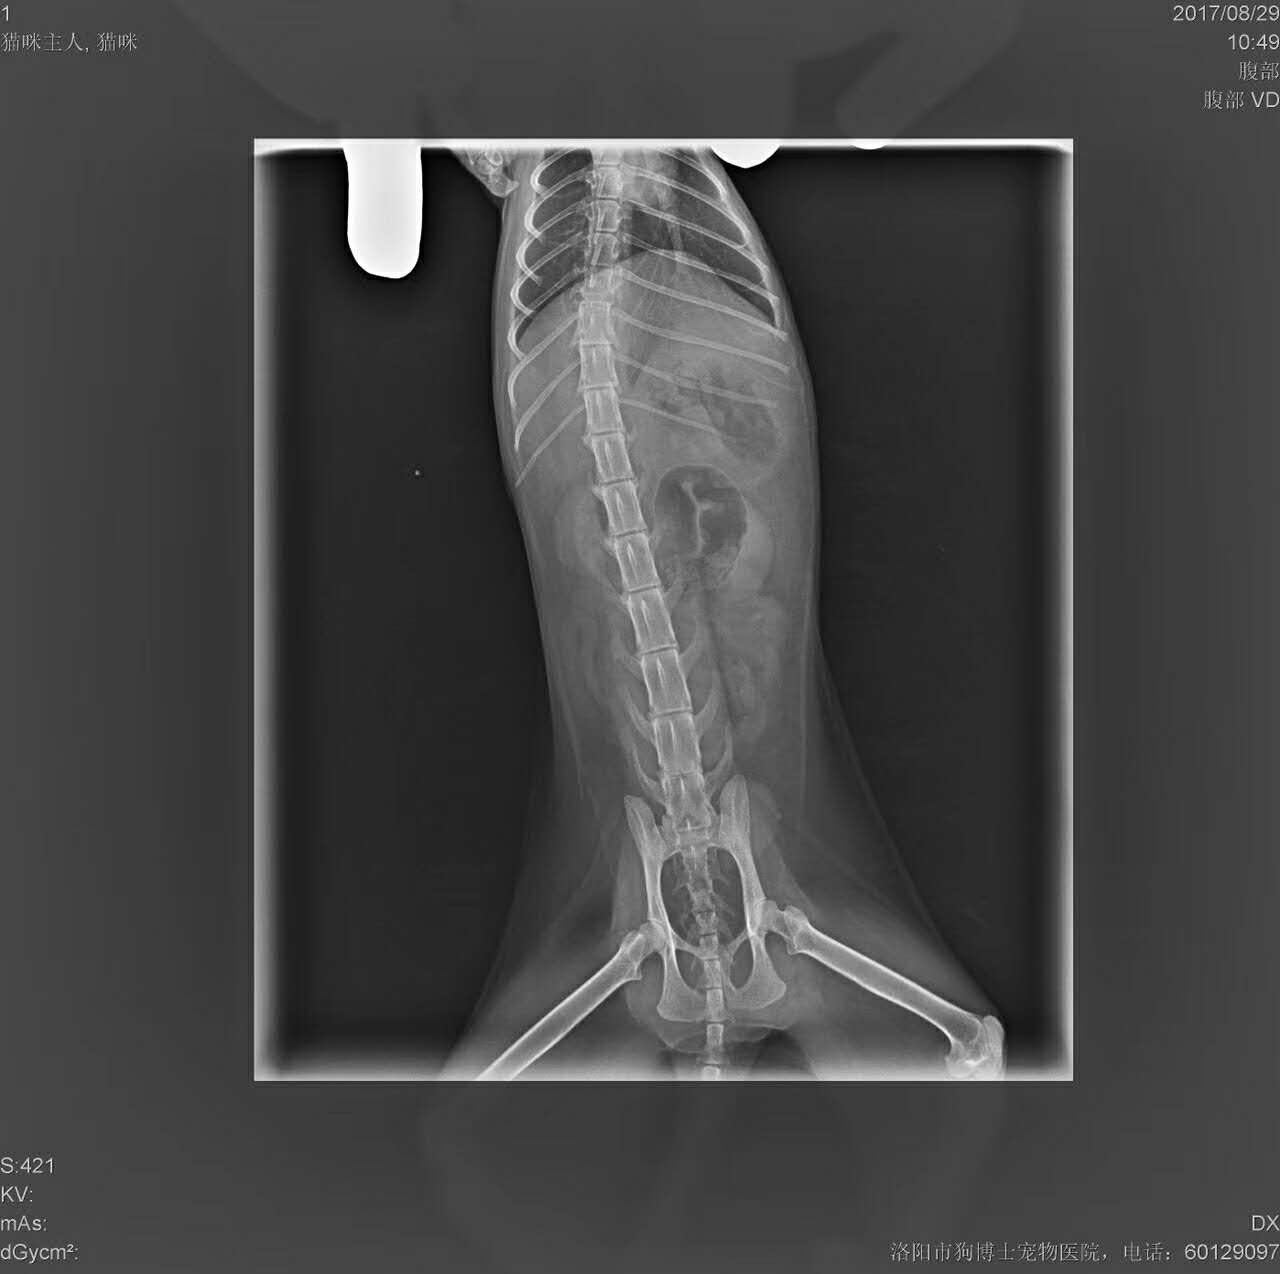

貓咪腸梗阻?絕育:貓咪,加菲貓混血兒,毛球引發(fā)腸梗阻,同時(shí)伴有嚴(yán)重肝臟,腎臟腫大(疑似長(zhǎng)期吃網(wǎng)購(gòu)貓糧引發(fā)),實(shí)施腸梗阻?絕育手術(shù),手術(shù)順利,但很擔(dān)心術(shù)后恢復(fù),體質(zhì)非常虛弱。